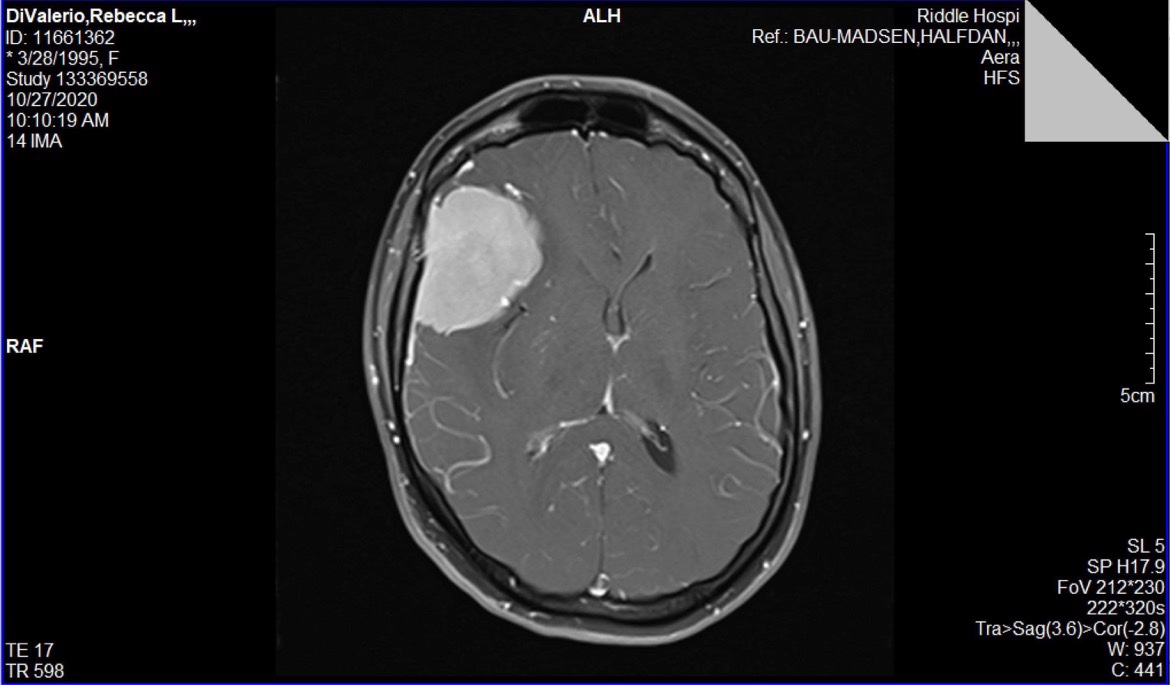

I added a photo of how big my tumor was for reference.